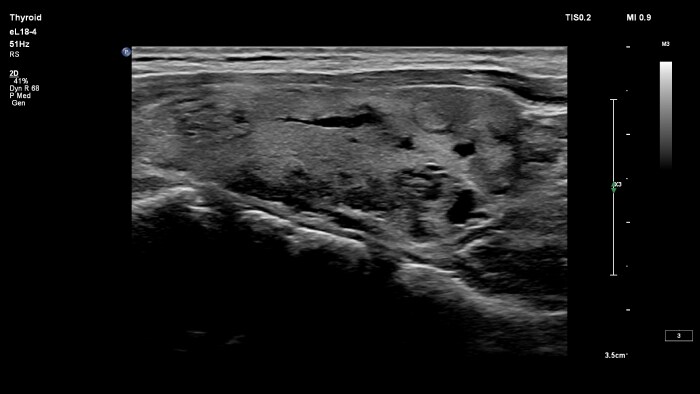

Small parts imaging is one of the fastest growing segments of ultrasound exams for clinicians around the world. Its wide array of applications includes assessing diseases and disorders of superficial organs like testicles and thyroid, as well as assessing musculoskeletal injuries like sprains and tears.

Thyroid ultrasound with

Dr Andrew McQueen

Dr Andrew McQueen of Freeman Hospital shares his experience working with the mL26-8 and eL18-4 ultra high-frequency linear transducers for neck ultrasound.